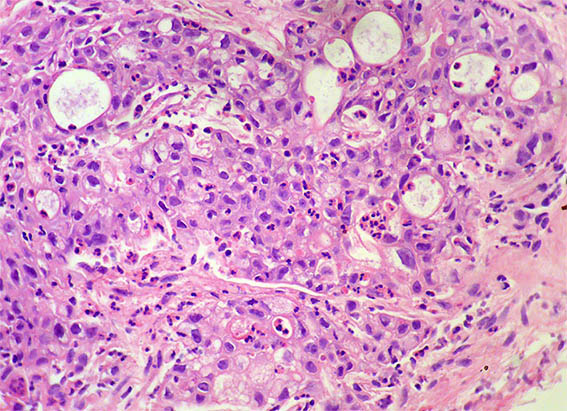

Figura 4. H&E, X200.